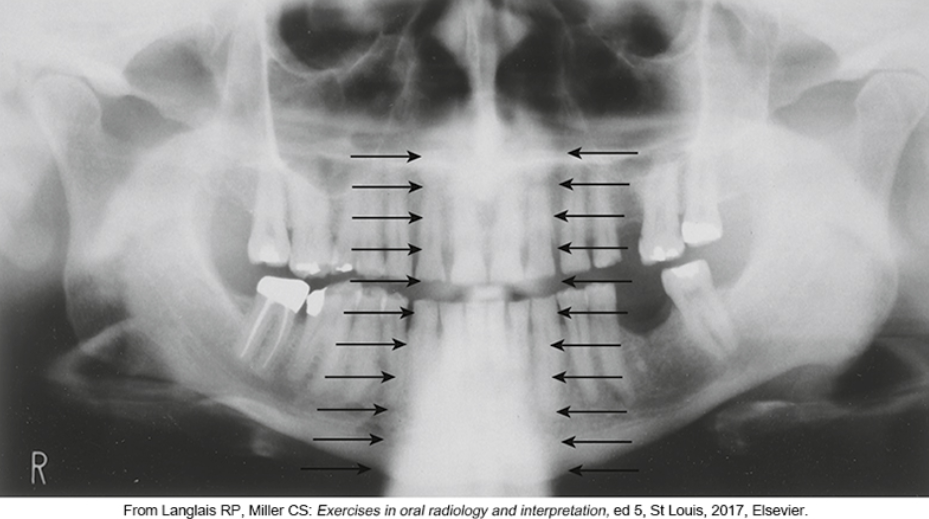

what is #2

what is #3

what is #4

what is #5

what is #6

what is #9

what is #10

what is #11

what is #12

what is #13

what is #14

what is #15

what is #16

what is #18

what is #20

what is #22

what is #23

what is #24

what is #25

what is #26

what is #27

what is #28